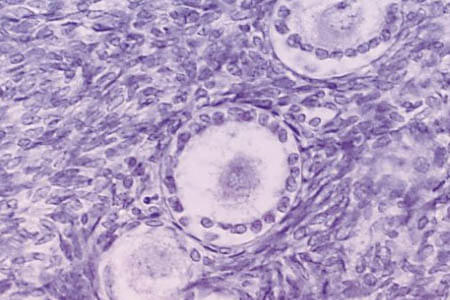

Гистологические изображения фолликулярной кисты яичника

Раздел: Лаборатория идей